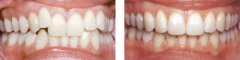

牙齿拥挤要怎么修复?

牙齿拥挤是常见的错合畸形,表现为牙齿拥挤错位排列不齐;而拥挤牙齿的龋及...【详细】

矫正牙齿拥挤需要拔牙吗?

牙齿拥挤是患者内心的一块石头,严重影响外观,还会影响身体健康,很多人因...【详细】